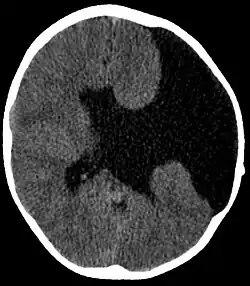

| Axial CT scan showing schizencephaly in a 6-year-old child | |

Schizencephaly (from Greek skhizein 'to split' and enkephalos 'brain')[1][2] is a rare birth defect of the brain, characterized by abnormal clefts lined with grey matter that form the ependyma of the cerebral ventricles to the pia mater. These clefts can occur bilaterally or unilaterally. Common clinical features of this malformation include epilepsy, motor deficits, and psychomotor retardation.[3]